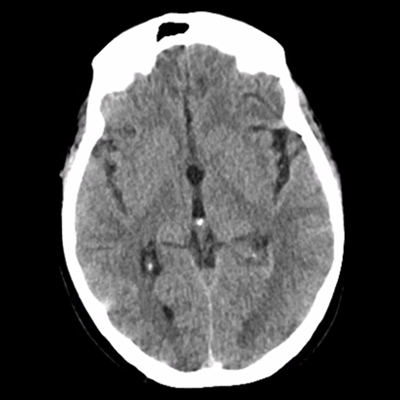

She woke up this morning and her legs "gave out" when she walked to the bathroom. Her hands shook bilaterally. She tried to speak, but her husband said she was "garbled" and nonsensical. Symptoms stopped once she got back in bed. She was able to speak short sentences. This episode lasted about two minutes in total. Her husband drove her to the ED. There, initial vitals are notable for BP 179/73, HR 63, SpO2 99% on room air, T 36.4C. Initial labs are notable for WBC 13, Hb 12, Plt 250, Na 133, Cr 0.7, uNa 179, uOsm 941, sOsm 274. A non-contrast HCT was obtained and is shown below. Her neurologic exam remains slightly abnormal: she is somnolent but does briskly awaken to verbal stimuli. She has no clear focal weakness or hypoesthesia. You were then consulted.

Looking at her non-contrast HCT now, there's nothing new in terms of acute hemorrhage or large-territory infarction, nor overt vasogenic edema. Now we should compare this to the prior scan. It's not shown well in these example slices shown here, but her ventricular caliber was very subtly larger as compared to the MRI, most noticeable with the slightly larger temporal horns and third ventricle.

Our leading diagnosis at this point is epileptic seizure. You hear that our neurology colleagues are already recommending repeat imaging and EEG, and they'll also start levetiracetam. Repeating an MRI is reasonable because she's already demonstrated cancer progression in spite of her therapy, and she's now having new symptoms. Her HCT doesn't clearly reveal anything that requires acute neurosurgical intervention. She has expected post-operative changes related to her frontal lobe metastasis resection. Her ventricles are questionably larger, but because of the temporal relationship with the steroid taper, you don't think this is responsible for her presenting symptoms. Her ependymal nodule certainly isn't the major contributor of her problems.